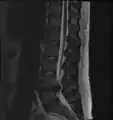

L'imagerie par résonance magnétique peut montrer la hernie, le canal vertébral, les nerfs, les tissus environnants. Les tissus mous sont les mieux analysés par cet examen qui est le plus performant pour le diagnostic de hernie discale. Les images pondérées en T2 montrent clairement la hernie.

IRM lombaire sagittale montrant une hernie discale de niveau L4-L5.

IRM lombaire sagittale montrant une hernie discale de niveau L4-L5.- IRM lombaire sagittale montrant des protrusions discales.